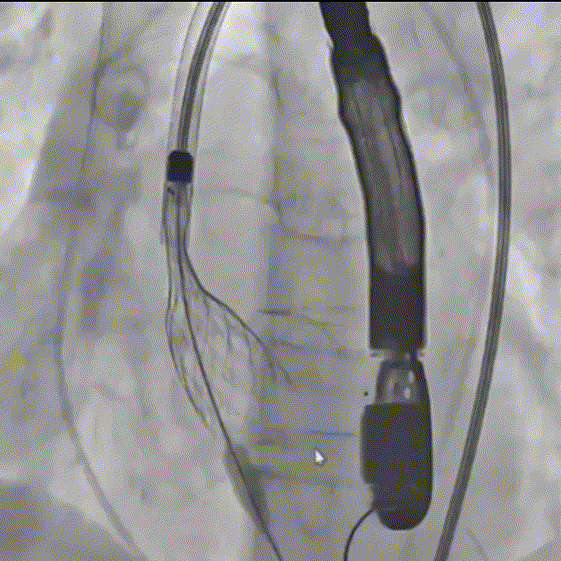

瓣膜一次稳定释放

瓣膜稳定脱钩

术后造影,瓣架形态良好